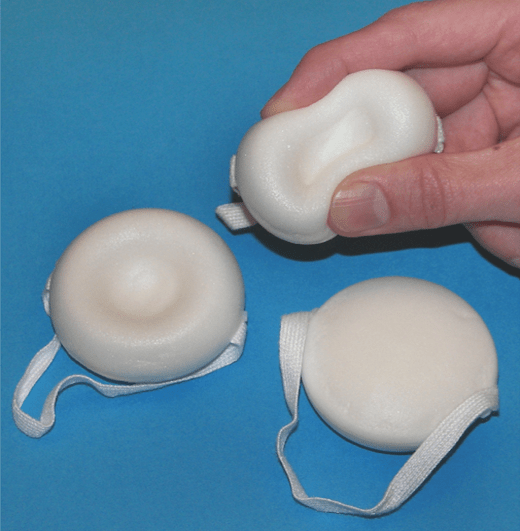

Los productos anticonceptivos como la espuma, crema, película, esponja, gelatina y supositorios están disponibles sin necesidad de receta médica en muchos lugares, debido a su facilidad de uso y accesibilidad. Estos métodos actúan principalmente a través de la inclusión de un espermicida llamado nonoxinol-9, el cual tiene la capacidad de destruir o inactivar los espermatozoides, impidiendo así la fecundación. Este espermicida no solo tiene propiedades espermicidas, sino que también presenta una actividad viricida y bactericida, lo que teóricamente podría ayudar a reducir la transmisión de infecciones.

A pesar de sus beneficios, la eficacia de estos métodos anticonceptivos no es absoluta, con tasas típicas de falla que varían entre el 10% y el 22%. Esto significa que, aunque sean efectivos para prevenir embarazos en un número considerable de casos, aún existe un riesgo significativo de fallo, especialmente si no se usan de manera consistente o adecuada.